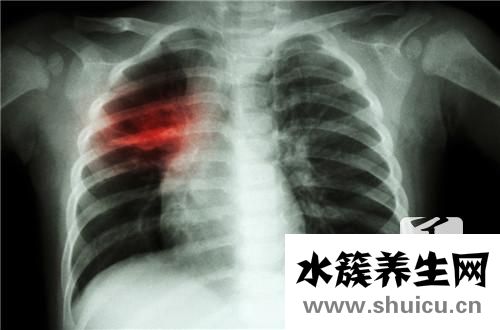

2、結核抗體陽性說明有結核分支桿菌感染,結核分支桿菌感染可以引起慢性的感染性疾病。呼吸道傳播的肺結核最為常見。它表現為長期低熱咳嗽、咳痰、咳血、進行消瘦等。常見的感染部位除了肺以外,還有胸膜、腹膜、心包膜、腦膜、淋巴結以及肝臟不、腸道、泌尿系統、骨結核和各個組織器官結核。但是,結核分枝桿菌培養陽性是結核病診斷的金標準。

3、結核病是結核分枝桿菌引起的全身各個臟器炎癥的慢性傳染病。最常見的是肺部的感染。此時體內會產生特異性的抗體。將結核分枝桿菌抗原包被在固相載體上,與待測的血清反應。血清中相應的抗體可結合于其上,再用膠體金或者酶標記顯示反應,可以檢測出血清中結核分枝桿菌的抗體。臨床上抗體陽性率為80~90%左右,表示有結核分枝桿菌感染,靈敏度超過90%,特異性超過85%。